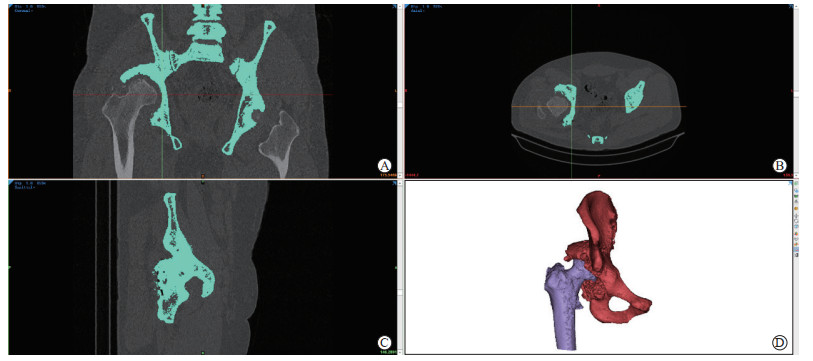

指导患者平卧在扫描床上,双腿伸直并轻微分开,同时保持髋关节在扫描范围的中心位置。选择适当的扫描参数(像素512×512,层厚1.0 mm)进行CT检查,将获得的CT数据以DICOM格式导入Mimics Medical 21.0软件重建模型。调整图像的方向,裁剪图像以去除不相关的区域。选定合适的灰度阈值,利用蒙罩编辑、擦除、填补、平滑等工具对骨骼进行细化填充,去除不需要的区域,填补空洞和平滑边缘;利用手工编辑图层工具擦除上述骨块表面凸起及补足其凹陷部分,修复模型表面的缺陷、去除不规则结构、优化网格的拓扑结构。初步建立原始髋关节3D模型,以STL格式导出并保存。结果如图 1所示。

图  1  骨盆CT扫描及原始髋关节3D模型初步重建

A~C:将CT扫描数据导入Mimics Medical 21.0软件;D:原始髋关节3D模型. CT:计算机断层扫描.